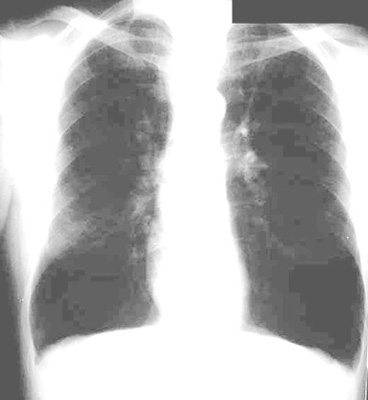

Emphysema/Alpha 1 Anti-Trypsin Deficiency

Vascular markings are not recognizable. Cephalization of vessels is not evident. Hyperlucent lung fields. Vertical Heart.

Increased AP diameter.